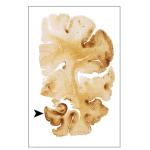

CTE

A study last week hit the news hard, like a linebacker, on the topic of Chronic Traumatic Encephalopathy (CTE) and football.